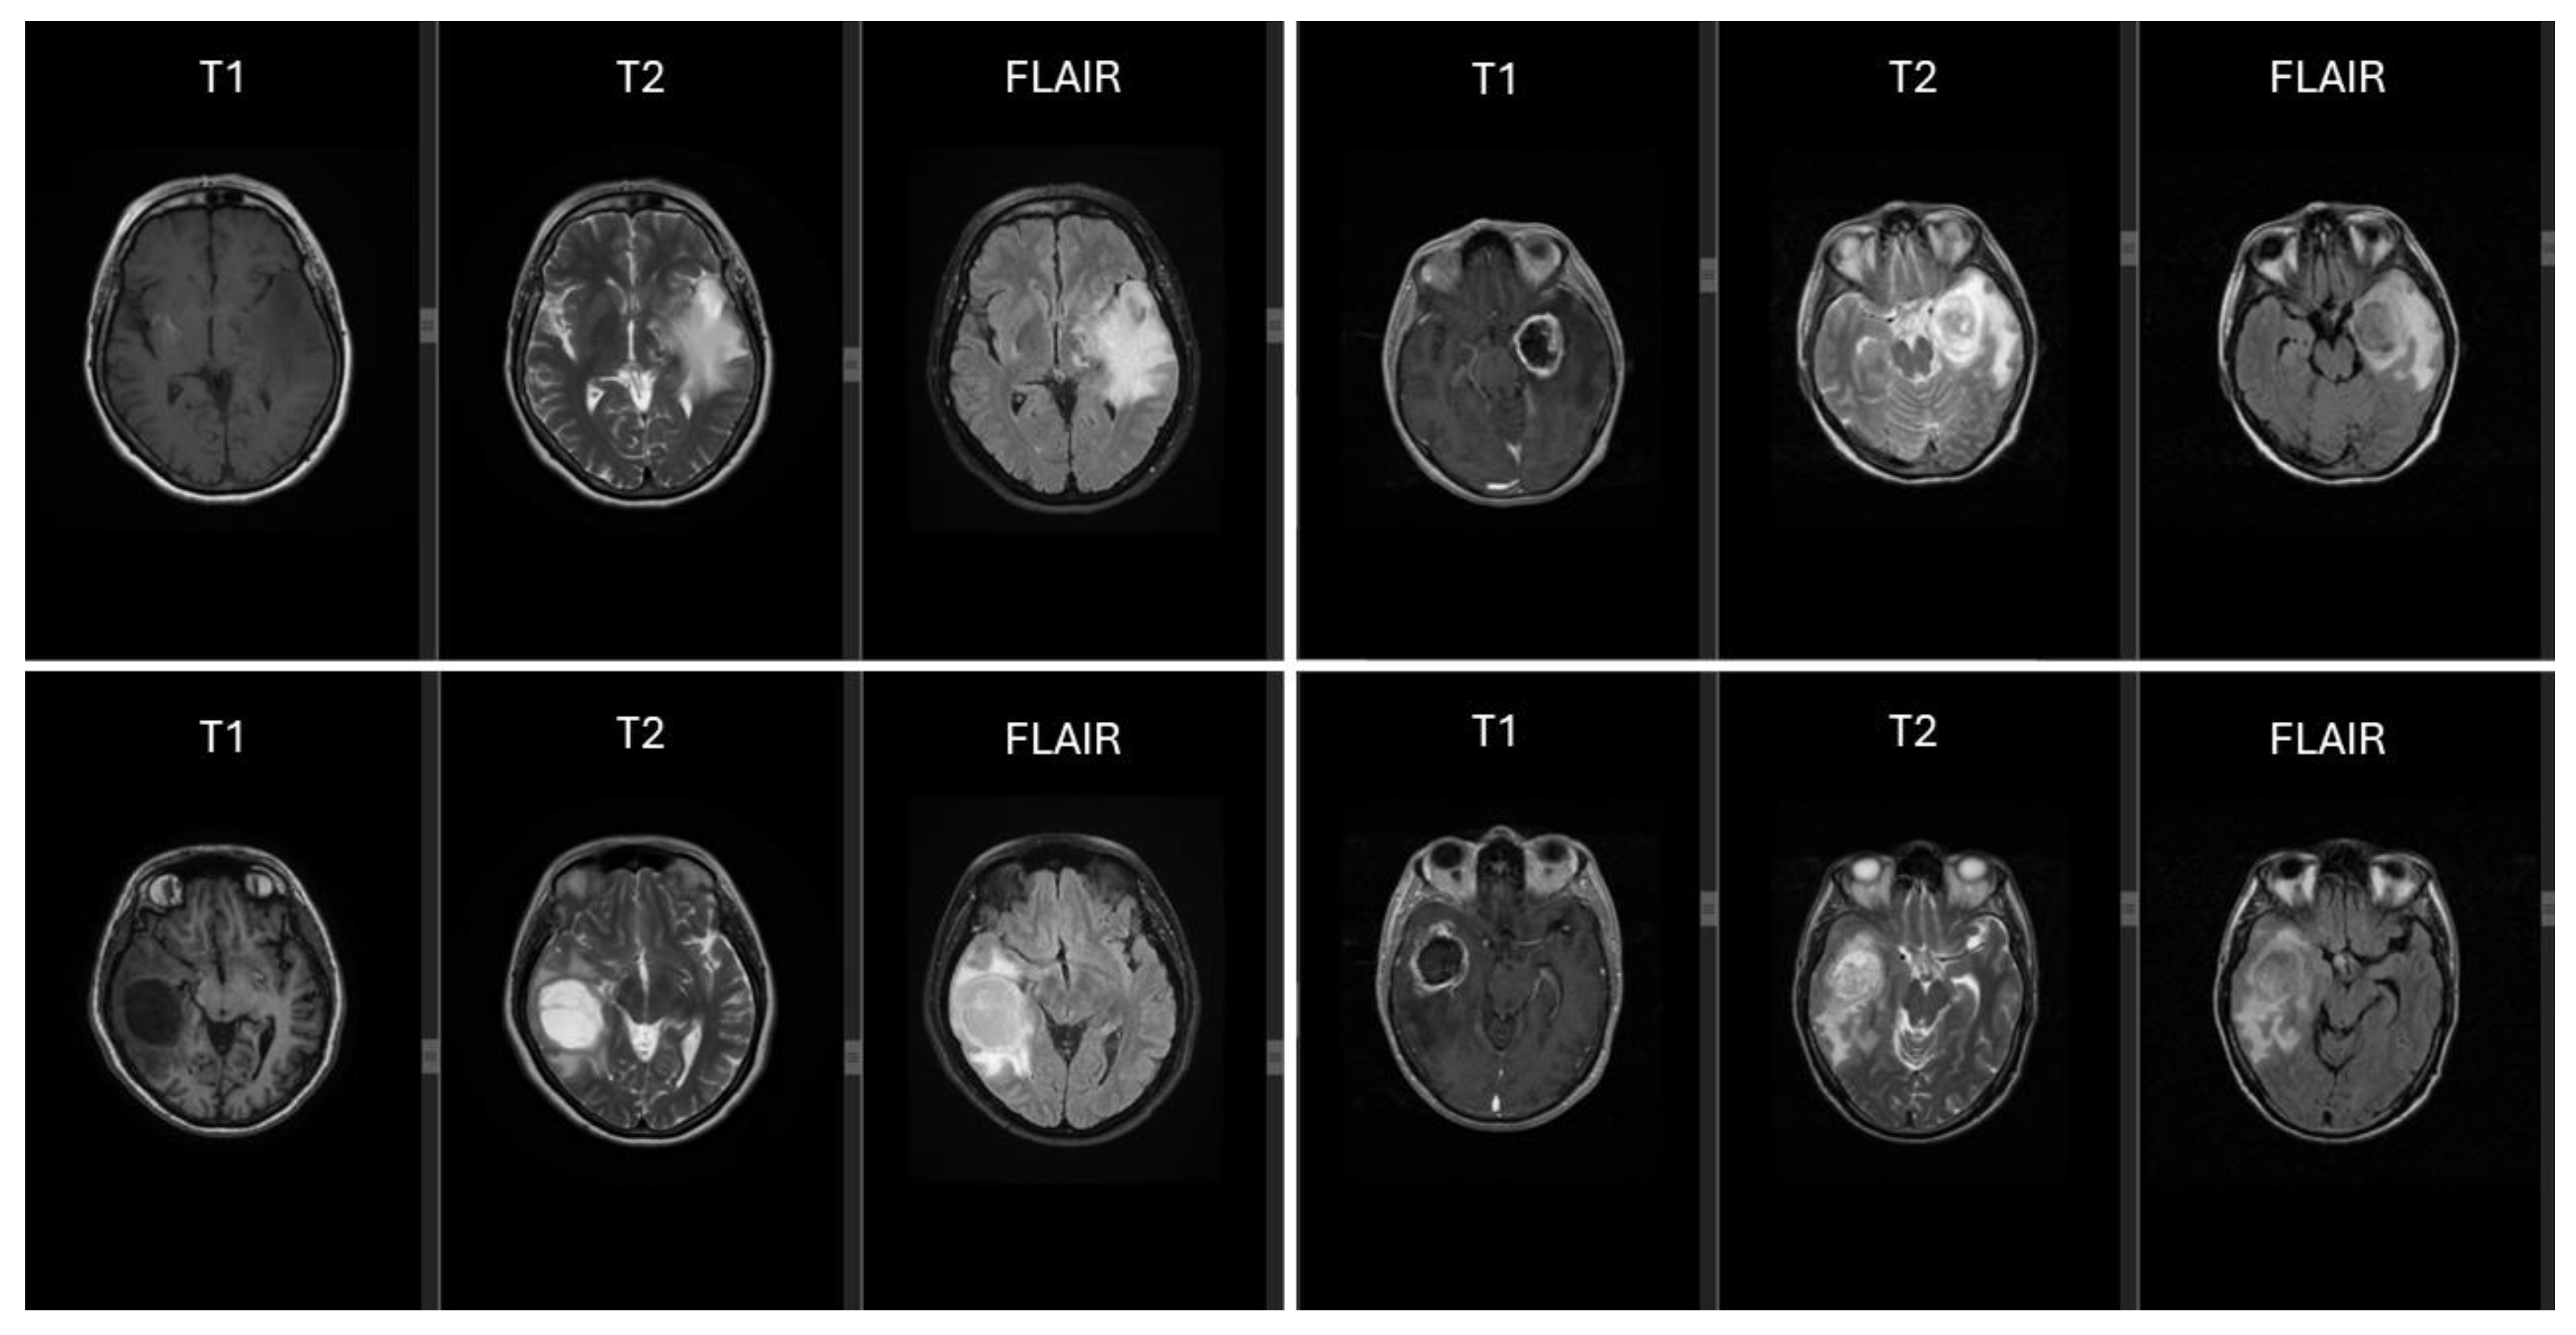

2.2. MRI Characteristics of Glioblastomas